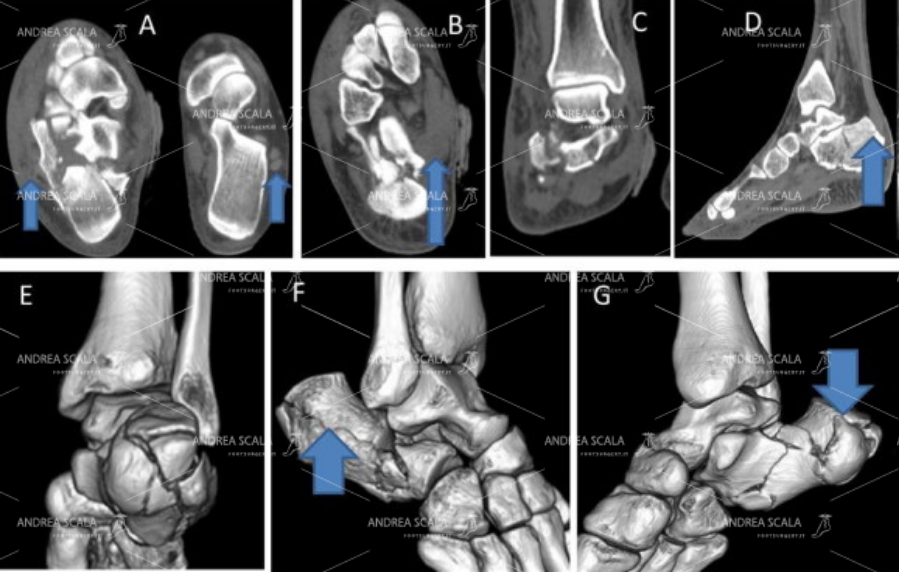

La Radiografia del piede fratturato è importante per mostrare che il calcagno non è normale, ma non è sufficiente. Quando si sospetta la frattura del calcagno occorre fare la TAC. La TAC mostra con precisione che dopo la frattura il calcagno è schiacciato, l’angolo di Bohler è appiattito, l’articolazione è spezzata, si vedono bene i frammenti della frattura.

La Radiografia non è sufficiente per capire la gravità della frattura del calcagno. E’ necessario fare la TAC. Dopo la frattura il calcagno è schiacciato, l’angolo di Bohler è appiattito, l’articolazione è spezzata, si vedono bene i frammenti della frattura.

La frattura di calcagno si vede nella RXgrafia, ma la TAC mostra ancora meglio come si è rotta l’articolazione e come sono spostati i frammenti. L’operazione deve ricomporre l’articolazione ed i frammenti della frattura. Si vede che i frammenti sono stati ricomposti uno a uno come un puzzle e sonno stati stabilizzati con placca e viti. Solo così il paziente può iniziare a camminare su di un piede ricostruito. Non bisogna fare pasticci con il “percutaneo”.